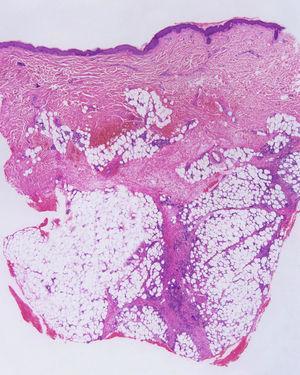

HistopatologíaLa lesión histopatológica característica del eritema nudoso es la paniculitis septal. Los septos están engrosados y hay un infiltrado de células inflamatorias que se extiende hasta las áreas periseptales de los lobulillos grasos (fig. 1). En ocasiones, este infiltrado parece extenderse hacia el centro del lobulillo y puede confundirse con una paniculitis lobulillar; sin embargo, a diferencia de ésta, nunca se produce necrosis de los adipocitos del lobulillo. El tipo de infiltrado varía en función de la antigüedad de la lesión. En las más tempranos hay predominio de neutrófilos que rodean los capilares y se pueden producir fenómenos hemorrágicos y edema. Este infiltrado se sustituye posteriormente por linfocitos, histiocitos, células gigantes multinucleadas, fibrosis y, en ocasiones, granulomas (fig. 2). Uno de los hallazgos histopatológicos más característicos del eritema nudoso es la presencia de los granulomas radiales de Miescher19,20. Constituidos por agregados nodulares de histiocitos en torno a un espacio de aspecto estrellado, se rodean de neutrófilos y están situados en el límite entre el septo afectado y el lobulillo. No se conoce la naturaleza de la estructura estrellada central de estos granulomas, y aunque se han considerado espacios linfáticos, estudios recientes han demostrado expresión de mieloperoxidasa y, por tanto, un posible papel de las células mieloides21. Son más habituales en las lesiones agudas, aunque pueden observarse en todos los estadios evolutivos y para algunos autores su presencia se considera un dato específico para el diagnóstico de eritema nudoso8; para otros, sin embargo, pueden haber lesiones similares en el síndrome de Sweet, eritema indurado de Bazin o en la enfermedad de Behçet22.